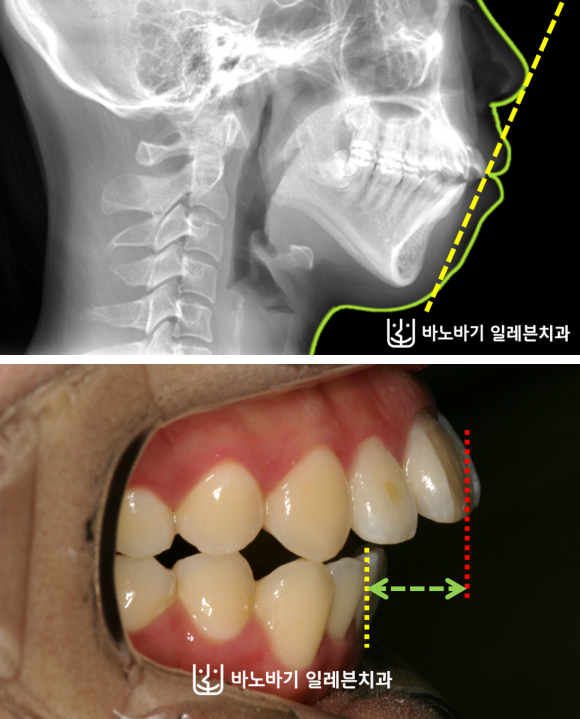

아래턱이 위턱보다 뒤에 있고, 상악 전치의 전방경사로 인해 입이 잘 다물어지지 못하는 증상을 보이고 있으셨습니다.

물론 외관상 단점도 관찰됐는데, 돌출입이 뚜렷한 편이었습니다.

게다가 입을 억지로 다물면서 입술에 힘을 주다 보니, 하악 이부 근육의 긴장감이 호두턱으로도 이어졌습니다.

무턱 때문에 발생하게 되는 전형적인 외모적 문제점이 이분에게서도 나타났습니다.

이밖에 앞니가 잘 닿지 못하며, 상악 우측 치열만 앞으로 나왔다는 점을 발견했습니다.

골격 불균형을 보완하기 위해 윗니 양쪽에 위치해 있는 제1소구치 2개를 발거하여 공간을 확보해주었습니다.

하악에서는 옆으로 누워버린 사랑니를 제거하였습니다. 상하로 각각 다른 곳을 뽑는 발치전략을 수립하였습니다.

이번 사례에서는 어떤 수술도 이루어지지 않았습니다. 상악 앞니의 전방경사를 적절한 수준으로 조정하면서, 전치부를 뒤로 움직였는데요.

이런 과정만으로 돌출입이 상당 부분 개선되었습니다. 윗니와 아랫니의 앞뒤간격도 굉장히 많이 줄어들었네요.

옆모습도 많이 좋아졌습니다. 입술이 자연스레 다물어지도록 만드는 데에 성공했습니다.